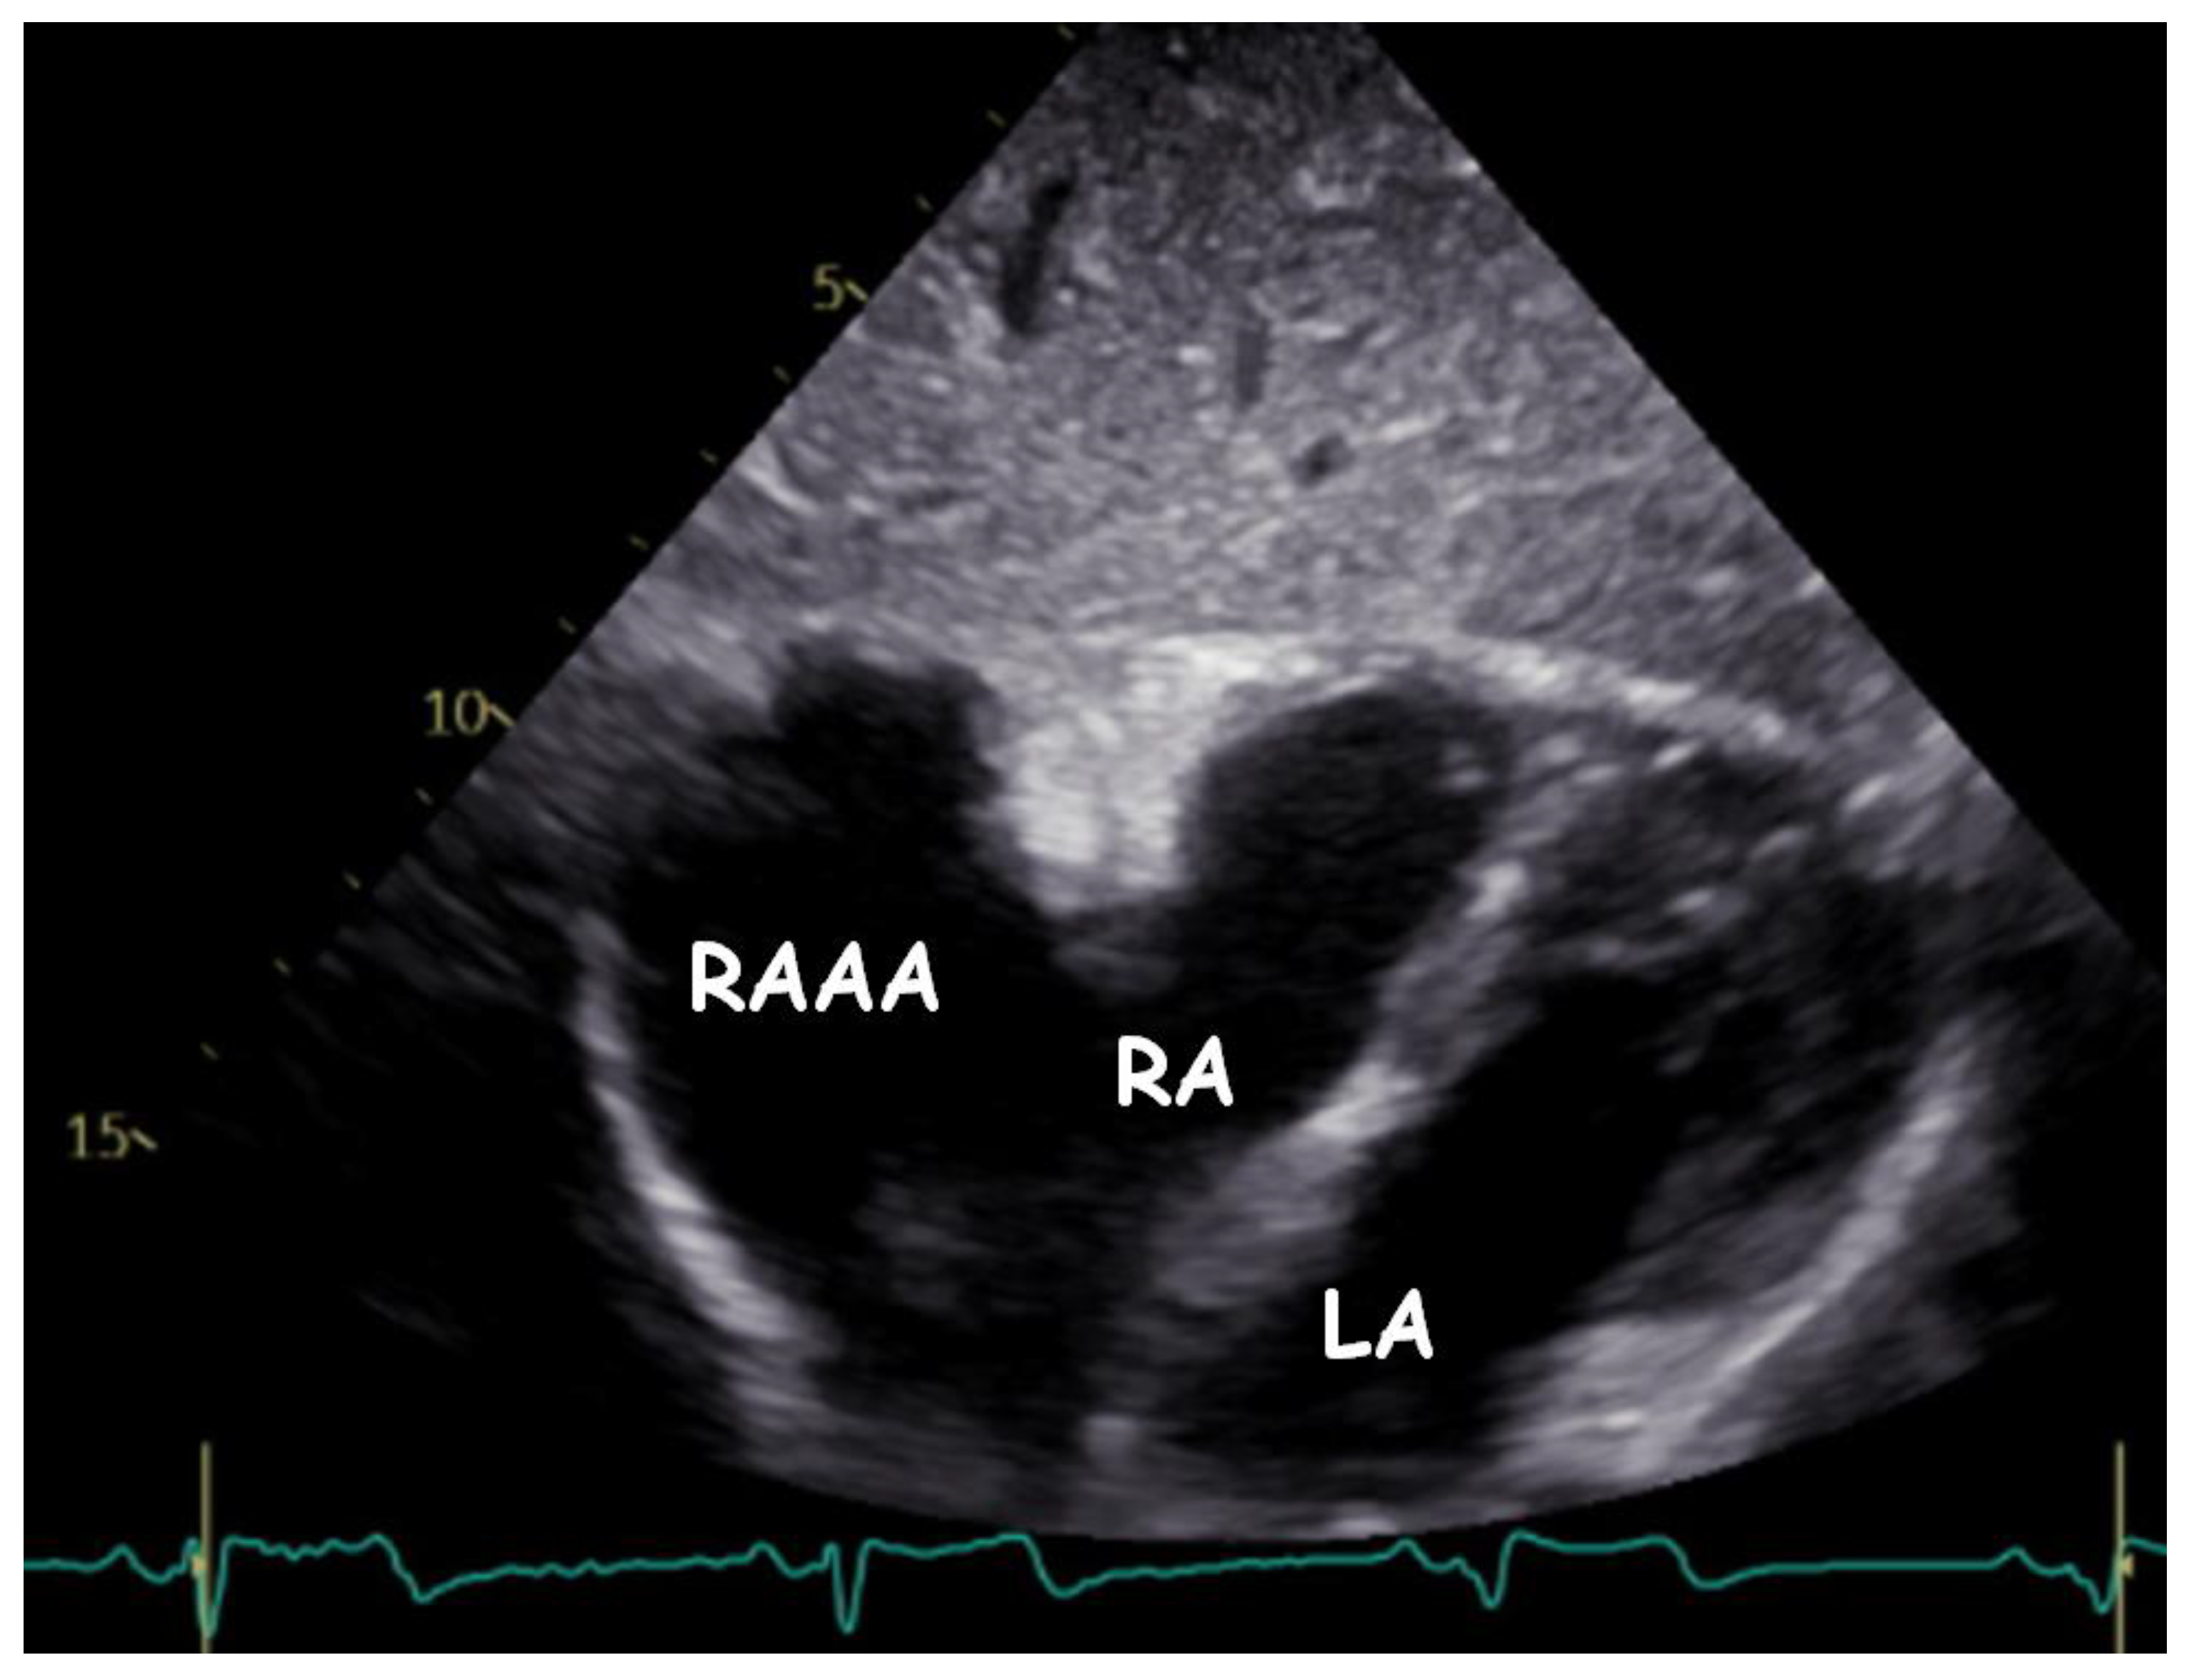

A Gigantic Congenital Right Atrial Appendage Aneurysm in an Infant: Ten-Year Follow-Up

1. Clinical Presentation

4. Follow-Up